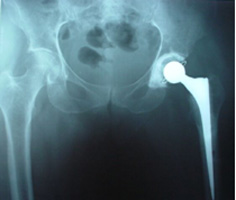

UNCEMENTED HIP REPLACEMENT

CEMENTED HIP REPLACEMENT